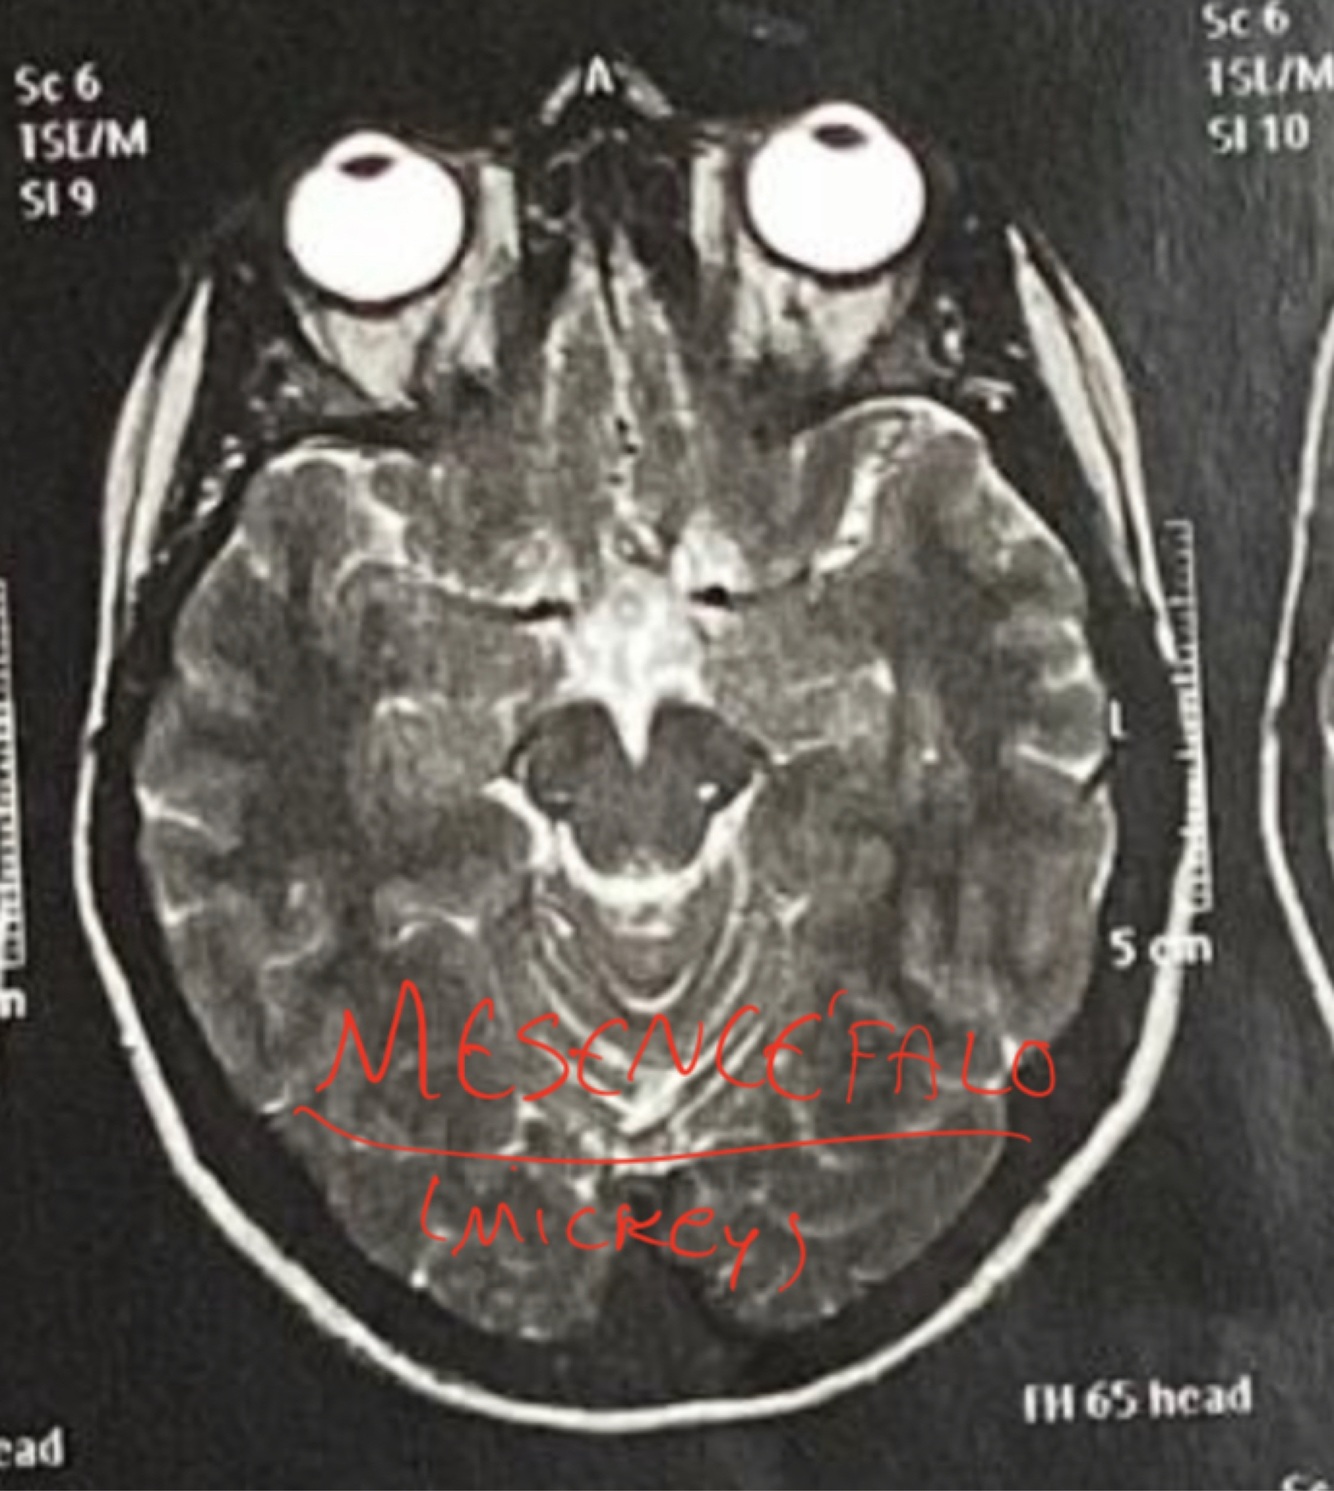

Q

RM Axial Bulbo

A

Michey